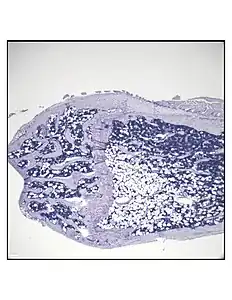

- Representative distal femur histologic section of a 16-week-old C57BL/6 mouse after 6 weeks of calorie restriction demonstrating an increased quantity of marrow adipocytes.